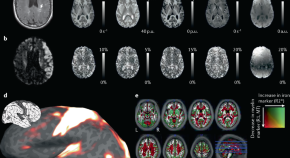

• Quantitative magnetic resonance imaging and in vivo histology go beyond standard magnetic resonance imaging, aiming at characterizing tissue microstructure of the living brain. This Technical Review discusses advances in concepts, instrumentation, biophysical models and validation approaches facilitating this rapidly developing field.

• Nikolaus Weiskopf

• Luke J. Edwards

• Evgeniya Kirilina

Technical Review